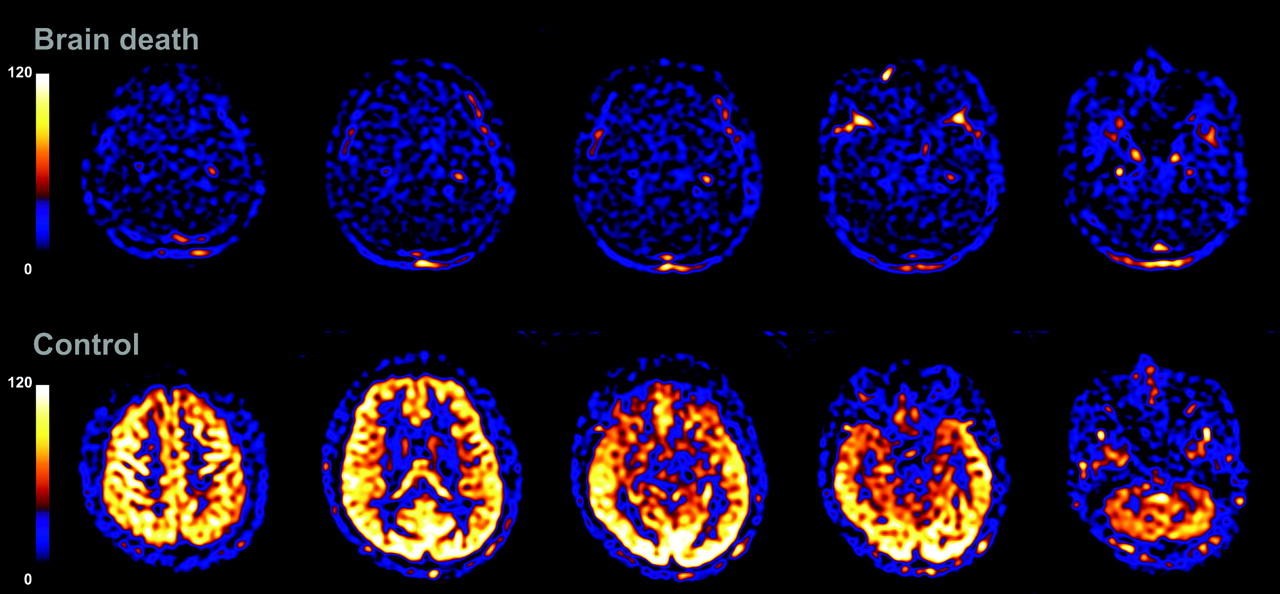

이주연은 사회적 고립, 노동 불안정, 기술 발전, 산업 독성학과 몸 정치학 등을 포괄한 광범위한 리서치와 인터뷰를 바탕으로, 분석적이면서도 시적인 논픽션 무빙 이미지를 연출한다.

Jooyeon Lee works with analytical yet poetic non-fiction moving image with expansive research and interviews to capture urban alienation, labour precarity, technological progress, industrial toxicology and body politics.